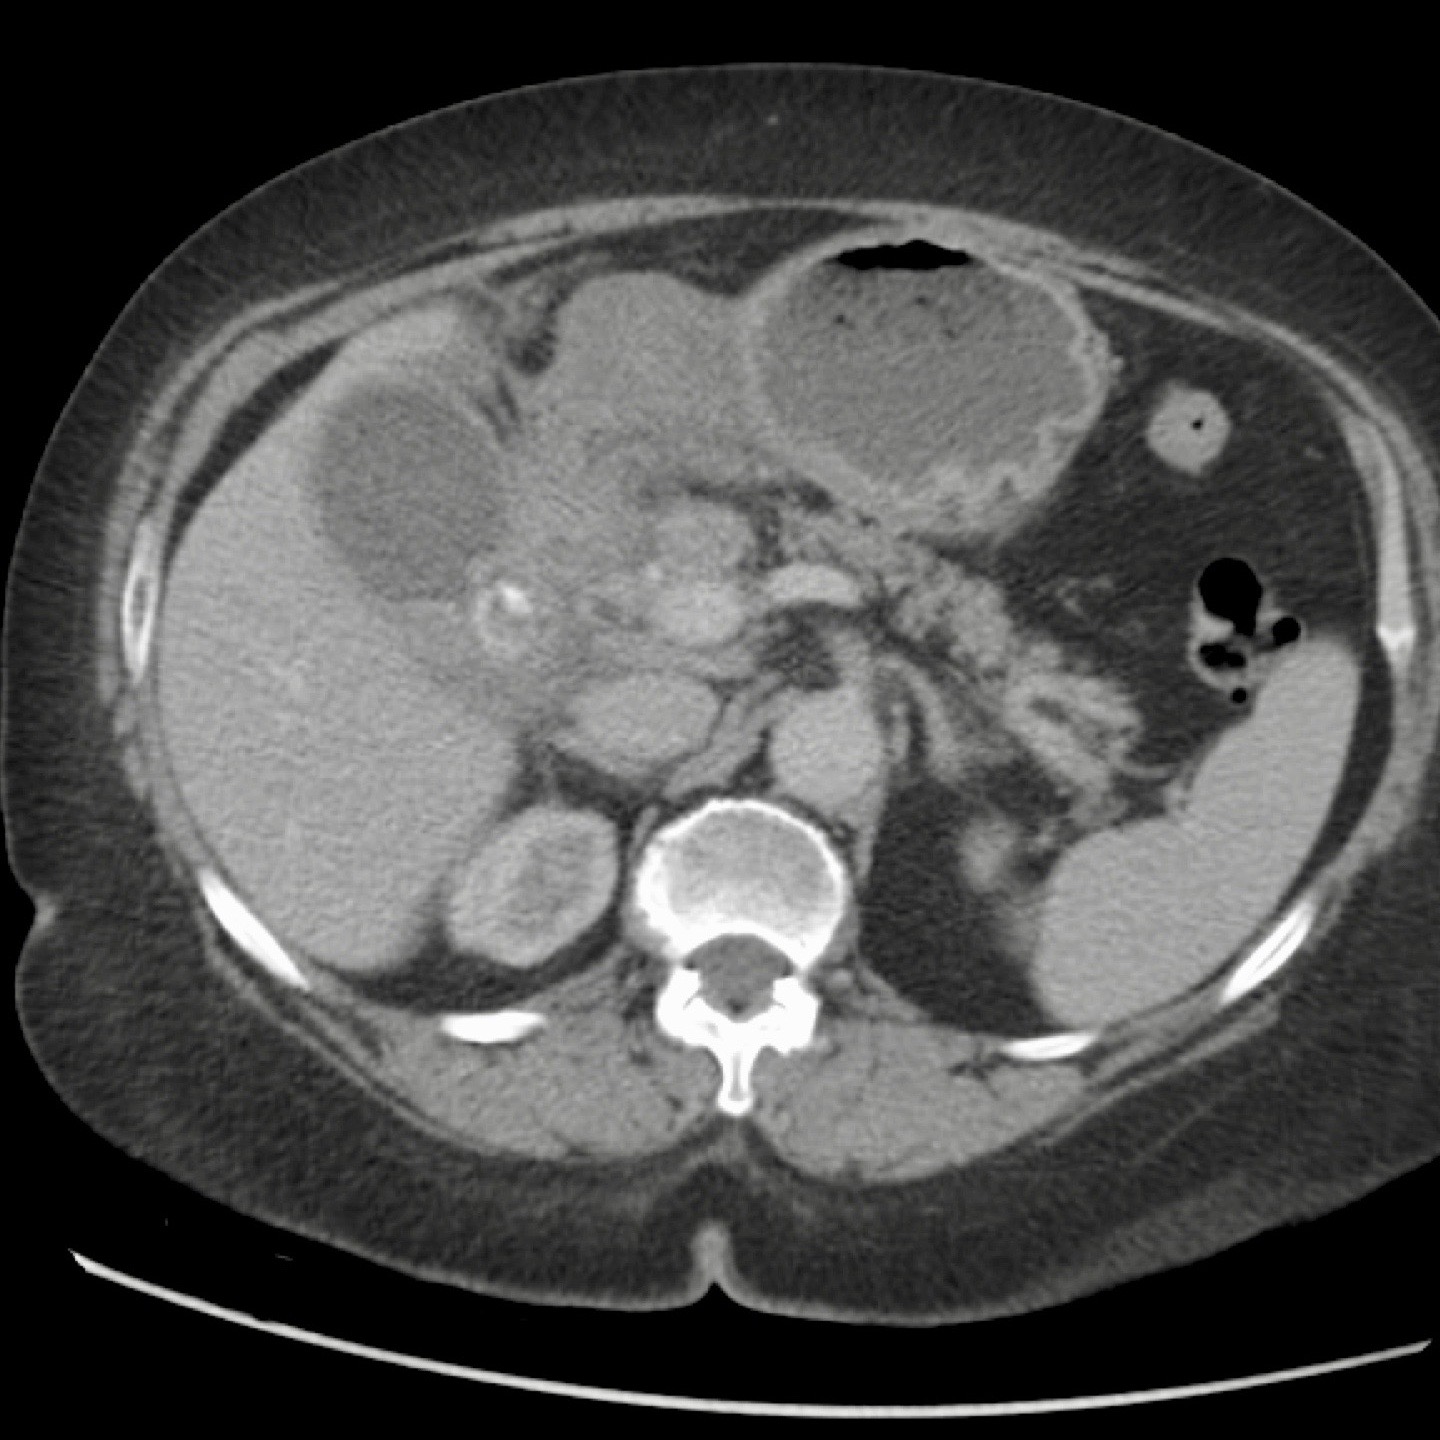

Bệnh nhân béo phì với đau thượng vị cấp tính.

Siêu âm cho thấy sỏi túi mật và dày thành, gợi ý viêm túi mật cấp.

CT thực hiện tiếp theo đã phát hiện bản chất thực sự của các triệu chứng: viêm tụy cấp do sỏi mật với dày thành túi mật thứ phát.